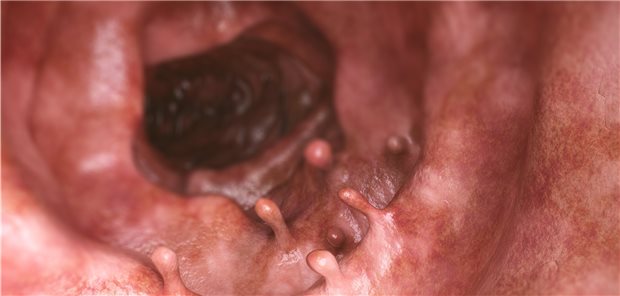

Kinder und Geschwister von Patienten mit kolorektalen Polypen haben ein erhöhtes Risiko, an Darmkrebs zu erkranken. Das gilt besonders für Karzinome, die vor dem 50. Lebensjahr auftreten.